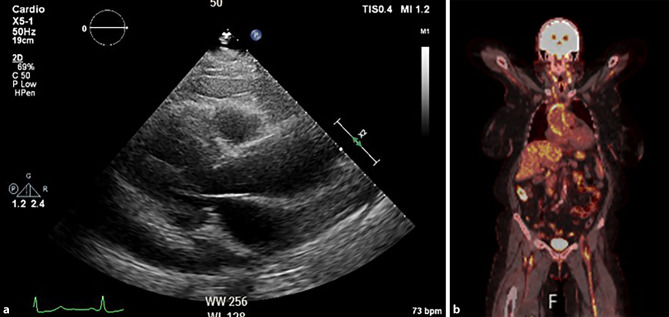

A cerebrovascular event turning pericarditis into vasculitis.

将心包炎转变为血管炎的脑血管事件。